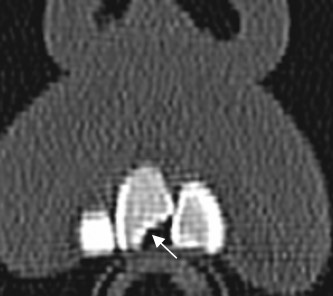

Fig 74 A. Fractura dental.

TAC reconstrucción coronal. Defecto en la parte interna del incisivo, por fractura.